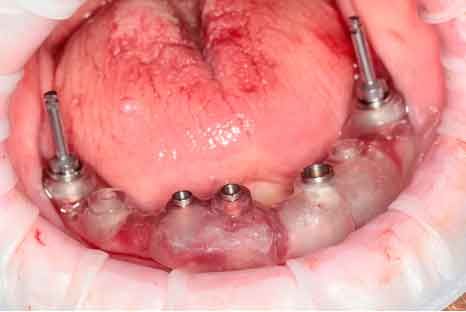

Picture - Initial bite situation

Before acquiring the CBCT, I added 2 pieces of composite to the mandible to be able to do the picking process during jaw motion recording. This is a useful trick to remember in a situation of lacking teeth.

Select 4 virtual points on the mandible of the imported bone mesh

Fix the fork (paraocclusal clutch) to the mandible of the patient

Pick the previously points in the patient's mouth using the Tally (stylus)